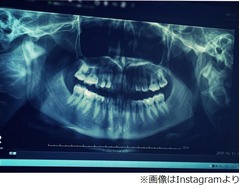

菜々緒はこの日、「#今日のすっぴん#27歳で衝撃の事実」として、歯のレントゲン写真を添えて「#先生いわく出っ歯らしい #噛み合わせの問題らしい」と、本人も初めて知った事実を赤裸々につづった。

そして「#いつの間にか出っ歯 #ふぁんたすてぃっく」と、驚いた様子を見せている。

これにファンからは「出っ歯!!まさかの(笑)」「笑っちゃいました(笑)」「すっぴんすぎますwww」「出っ歯仲間ですね(笑)」「これはマニア向けだな」などの反応のほか、「親知らず抜いた?」「顎関節右あごのほうが太くなってる」「神経抜いた歯がまだ一本もないですね」「菜々緒さんのパノラマ見れるとは思わなかった」「パノラマテンションあがります!」といった歯科関係者と思しき人たちからのコメントが多々寄せられている。